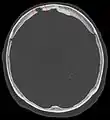

Безконтрастна КТ голови показує пахіонові грануляції.